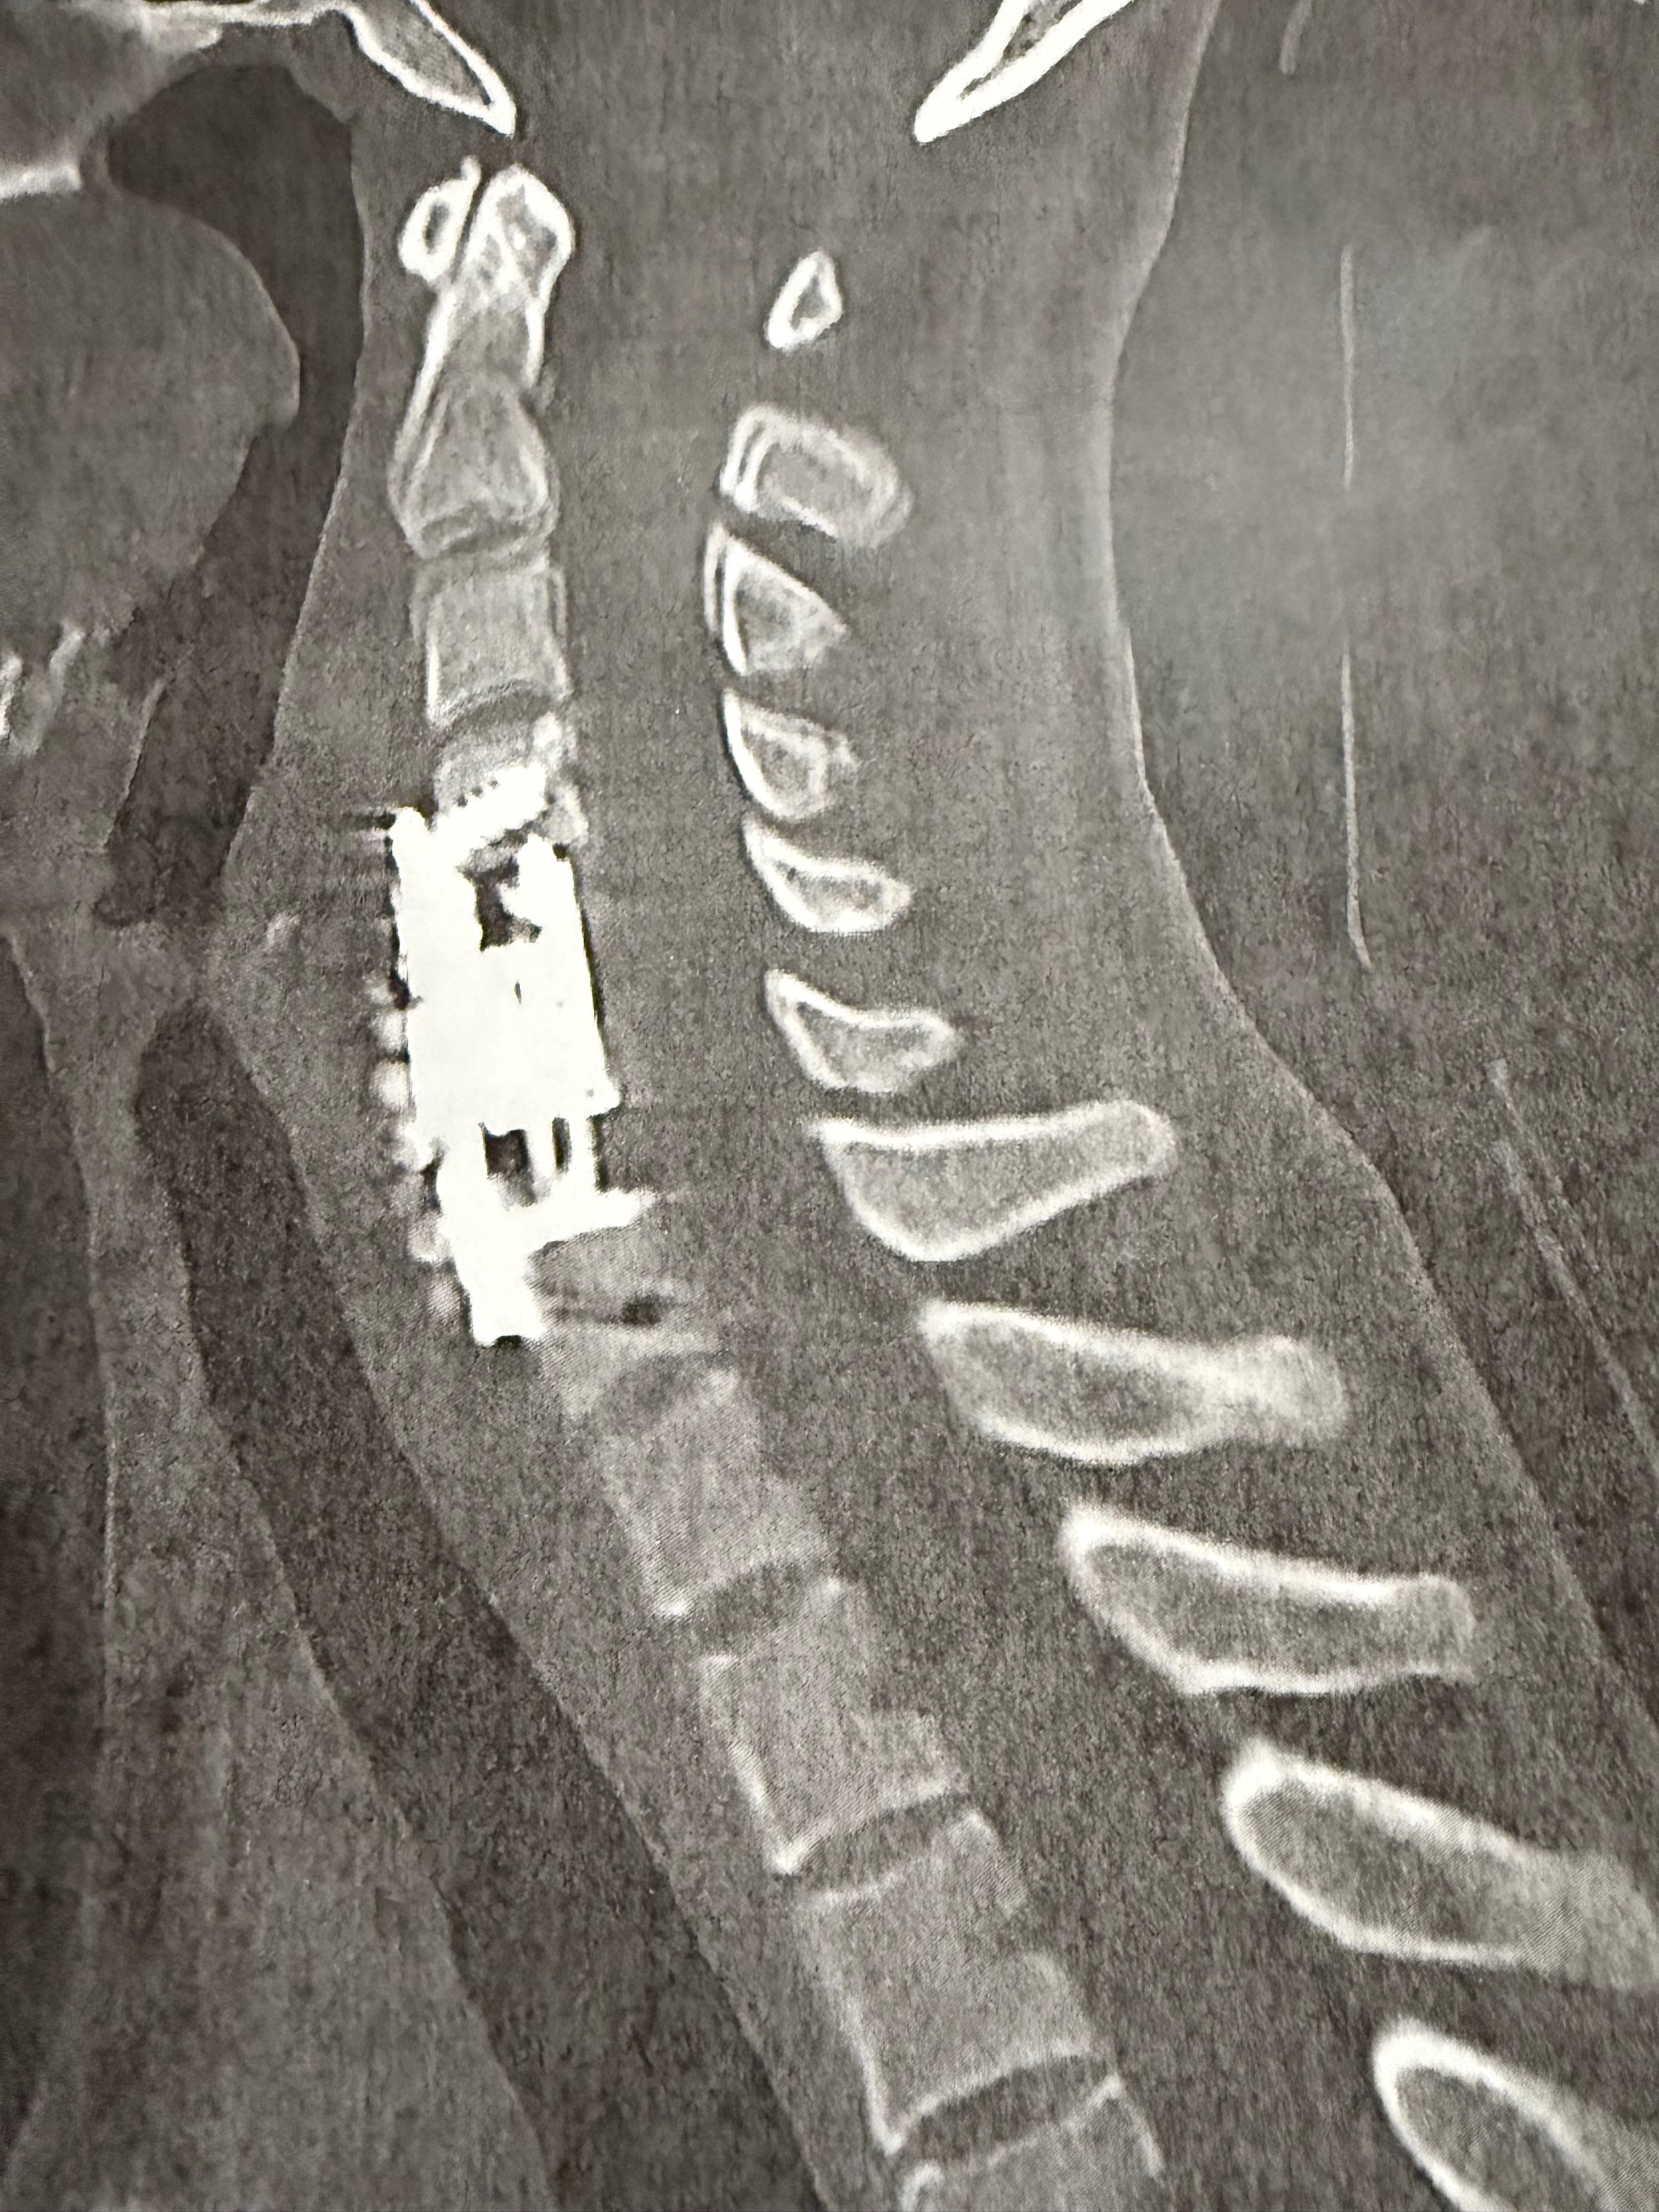

Rebecca is a mother of 2 young children, living in a 1 income household. After being shuffled around local health care facilities for over a month MRI imaging revealed a “complete collapse” of her C5+C6 bones in spinal column causing near full internal decapitation as well as infection. Immediate emergency surgery was needed upon hospital admission, with the only other outcome being unfortunate death. 2 spinal surgeries, 6 weeks of IV antibiotics via PIC, physical therapy and months of intensive care/healing leaves Rebecca inpatient with a discharge date that is yet TBD and unable to work for 4 to 6 months. The only income for the entire household has already suffered a massive financial cut through the holidays